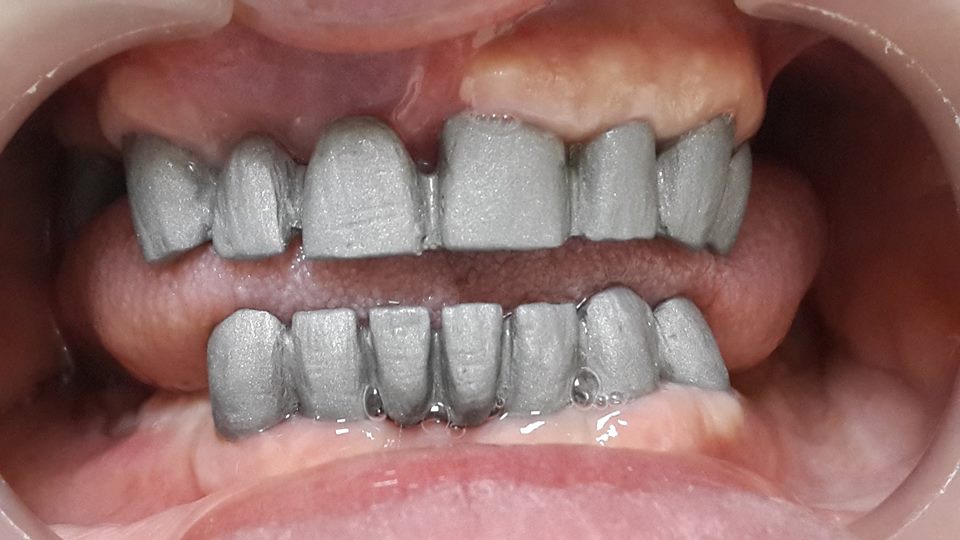

An example of complete rehabilitation of the oral cavity. Treatment included the removal of the old prosthesis, treatment of paradontitis, removal of a large cyst, implantation, clasp prosthesis.